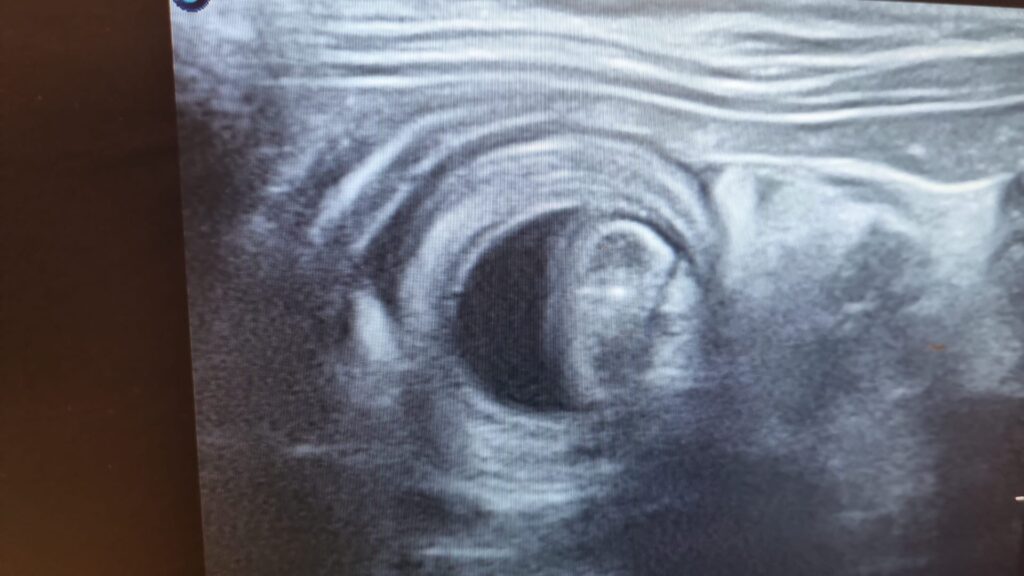

Wykonujemy badania ultrasonograficzne:

– jamy brzusznej,

– tarczycy,

– diagnostykę ciąży,

– badania w protokołach TFAST oraz AFAST (w stanach nagłych).

Badania obrazowe stanowią istotny element wczesnego wykrywania zmian chorobowych oraz monitorowania leczenia.